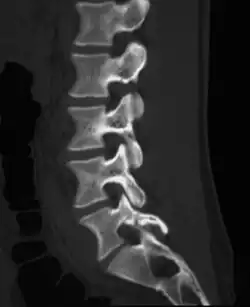

La spondylolyse est une perte de continuité de l'isthme articulaire (pars interarticularis), situé entre les deux apophyses articulaires supérieure et inférieure de l'arc vertébral postérieur. Elle survient le plus souvent au niveau d'un étage vertébral lombaire bas, habituellement le dernier étage mobile. Elle peut être unilatérale ou bilatérale, induisant alors une micro mobilité ou une mobilité de l'arc postérieur. Elle peut être aigüe, traumatique, correspondant à un trait de fracture vrai, ou chronique, sans notion de vrai traumatisme. La perte de continuité s'organise alors sous la forme d'un tissu fibreux ou plus rarement pseudo kystique plus ou moins hypertrophique dit « nodule de Gill », qui peut être agressif pour les racines nerveuses au contact. La lyse peut survenir dans l’enfance, mais aussi à l’âge adulte.